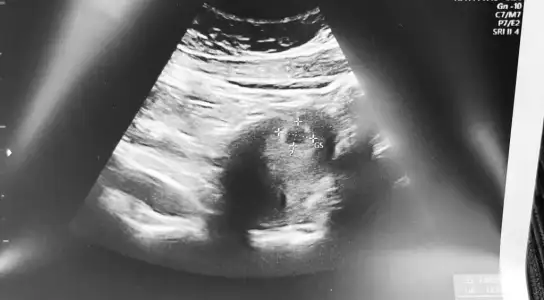

Bende ayni durumdayim 6 haftalik kese 12mm yolkta var ama bebek yok :KK43: insallah 10 gune olusur.mucizem benle kalir:KK43: seninde oyle insallah💜💜

Eklentiler

• 1C936A91-85F2-4BCC-BEBD-B73FD9B08A71.webp

1C936A91-85F2-4BCC-BEBD-B73FD9B08A71.webp

35 KB · Görüntüleme: 229